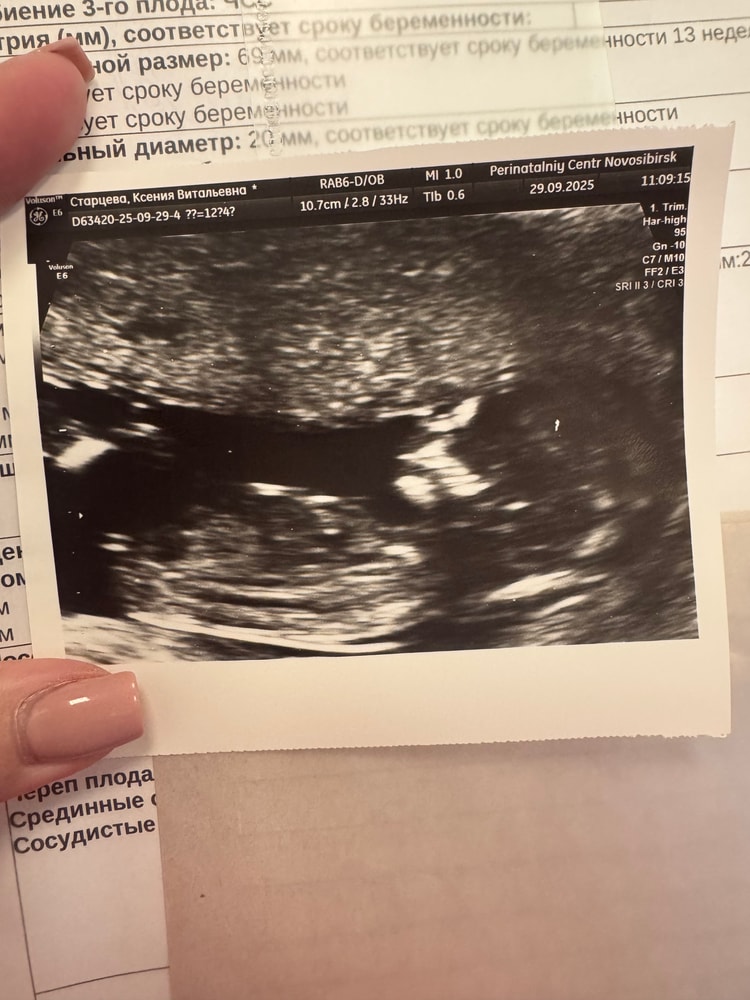

Результаты: УЗИ, КТГ, доплера, скринингаНу вот сегодня прошла узи так все в норме. Но в выписки увидела заключение: предлежание плаценты внутренний зев перекрывает на 18мм. Странно в кабинете мне ничего про это не сказали. Чувствую себя хорошо,нет никаких выделений 🙏🏻к гинекологу после завтра только. Было ли у вас такое и нормально ли это?